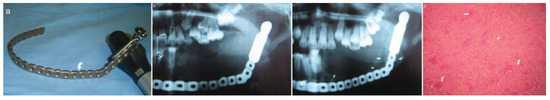

New Bone Formation After Ligation of the External Carotid Artery and Resection of a Large Aneurysmal Bone Cyst of the Mandible with Reconstruction: A Case Report

by Colin Perumal, Ashraf Mohamed and Avin Singh

Craniomaxillofac. Trauma Reconstr. 2012, 5(1), 59-63; https://doi.org/10.1055/s-0031-1293519 (registering DOI) - 27 Oct 2011

The aneurysmal bone cyst (ABC) is a benign cystic and expanding osteolytic lesion consisting of bone-filled spaces of variable size, separated by connective tissue containing trabeculae of bone or osteoid tissue and osteoclast giant cells. Radiographic findings may vary from unicystic or moth-eaten radiolucencies to extensive multilocular lesions with bilateral expansion and destruction of mandibular cortices. Treatment modalities include curettage (with reported recurrences) and resection with immediate reconstruction. The main arterial and feeder vessels may be embolized to prevent profuse intraoperative blood loss and achieve a bloodless surgical field. Failed embolization may necessitate ligation of the external carotid artery of the affected side. Full article

Show Figures

Figure 1